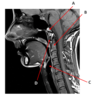

Which structure is labeled by E?

Cricoid cartilage

Which artery is labeled by B?

Maxillary artery

Where in the neck does the common carotid artery split into the internal and external carotid arteries?

At the level of the upper border of the thyroid cartilage

(Around C3/C4)